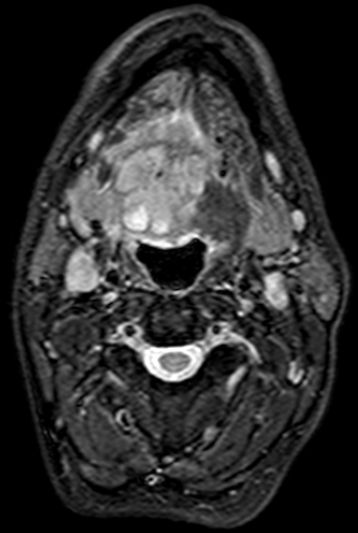

| MRT | 64jährigen Bauingenieur mit einem Mundbodenkarzinom rechts cT4 cN2 M0. Vor 7 Wochen leichte Schwellung unter der Zunge. Am Unterkiefer adhärenter maligner Prozess. Keine Infiltration knöcherner Strukturen. Metastasensuspekter Lymphknoten an der Karotisbifurkation rechts. | ||